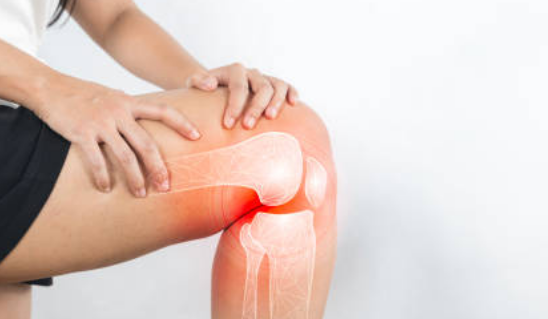

골다공증이 진행되면 어떤 위험이 있나요?

골절, 만성 통증, 신체 활동 제한 등이 발생할 수 있으며, 골절이 회복되지 않을 경우 심각한 합병증이 생길 수 있습니다.

체중 부하 운동(걷기, 등산, 체조), 근력 강화 운동(웨이트 트레이닝, 저항 밴드 운동)이 뼈 건강에 도움이 됩니다.